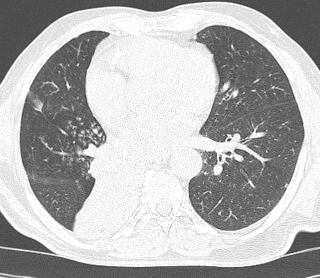

Evidence of complete collapse of the right lower lobe evidence in scout film as well as axial sections with no obvious air bronchogram. There is abrupt cut off of the left lower lobe bronchus. There are acinonodular shows in the perihilar region and right middle lobe along with interlobular septal thickening. These findings particularly in view of age and bronchial cutoff are suspicious for mitotic etiology. Bronchoscopic and histopathological correlation are suggested.